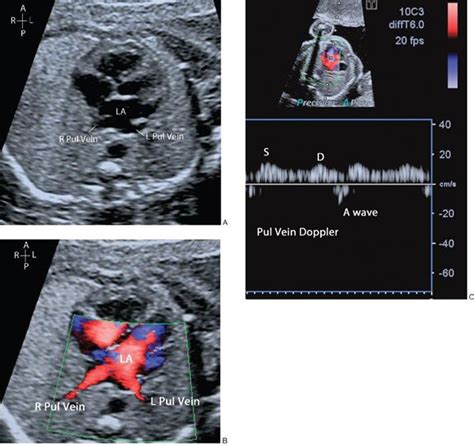

There are other views too, guys! The sonographer might also use views to assess the inferior vena cava (IVC) and the superior vena cava (SVC), which are major veins that carry blood back to the heart. They might also look at the aortic arch and the ductus arteriosus. The ductus arteriosus is a blood vessel that connects the pulmonary artery to the aorta in a fetus, and it’s essential for blood circulation before birth. These views help to provide a complete picture of the baby’s circulatory system. The specifics will vary depending on the baby’s position and any concerns the doctor may have. The key is that the sonographer adapts the examination to get the clearest, most comprehensive picture possible.